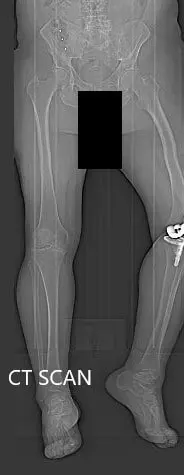

Preoperative topography CT scan images of the lower extremities

Preoperative topography CT scan images of the lower extremities - img 2

Preoperative topography CT scan images of the lower extremities.

A preoperative CT scan was obtained a few weeks prior to the procedure. Detailed models of the patient’s anatomy were constructed. Accurate bone cuts and offsets were determined to preplan the surgery. Disposable unique jigs and customized implants were made to match the patient’s anatomy.